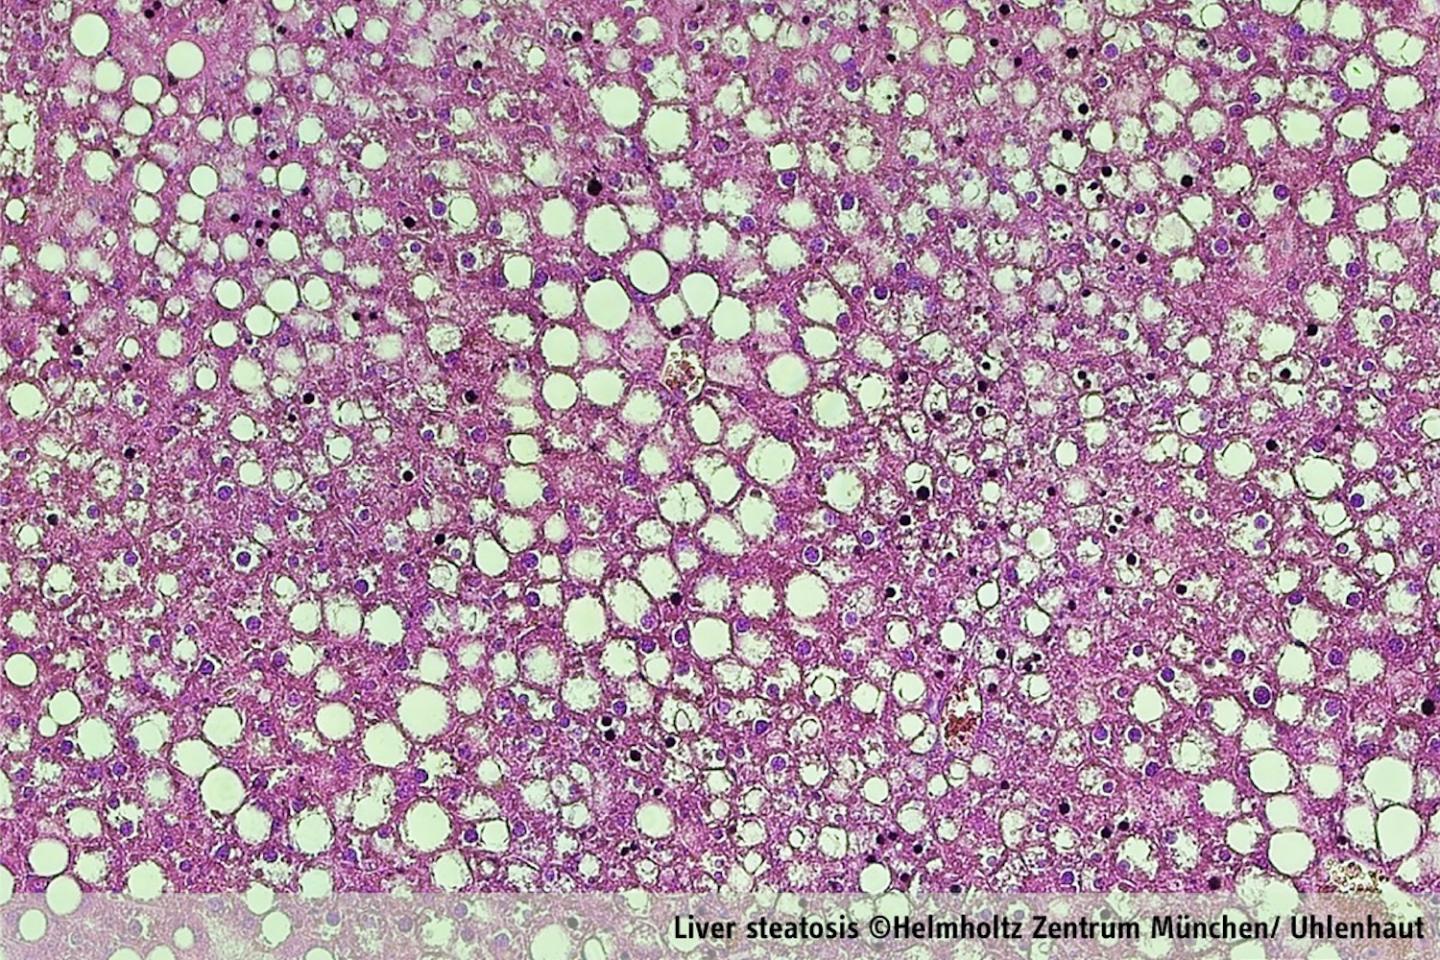

The research conducted in mice found that the time-of-day dependent metabolic cycle is altered by high caloric diet. Since glucocorticoids are widely used drugs for the treatment of inflammatory diseases, these findings published in Molecular Cell suggest that lean and obese patients might respond differently to steroid therapy. Finally, it reveals the biological function of daily rhythms of hormone secretion (high before awakening and feeding, low when sleeping and fasting) as well as daily cycles of sugar and fat storage or release by the liver.

Each cell in the human body is driven by an internal clock which follows the circadian rhythm of 24 hours. It is synchronized with the natural cycle of day and night mainly by sunlight, but also through social habits. In a healthy system, glucocorticoid stress hormones, are produced every morning by the adrenal gland. The secretion of glucocorticoidpeaks before awakening, prompting the body to use fatty acids and sugar as sources of energy, and enabling us to start our daily activities. When the circadian rhythm is disrupted (e.g. through shift work or jetlag) and/or when the glucocorticoid level alters (e.g. through Cushing syndrome or long-term clinical application), profound metabolic dysregulation can be caused - like obesity, type 2 diabetes, and fatty liver disease. The researcher's goal therefore was to understand the relevance of these daily peaks of stress hormone secretion, the impact of these hormones on our "internal clock" and their role for daily cycles of metabolism.

To study glucocorticoids' metabolic actions in the liver, the researchers characterized the activity of their receptor, called the glucocorticoid receptor, using novel high throughput techniques. They analyzed mouse livers every 4 hours during day and night. The mice were either in normal condition or fed with high-fat diet. They then used cutting-edge technologies in genomics, proteomics, and bioinformatics to picture when and where the glucocorticoid receptor exerts its metabolic effects. The researchers dissected the impact of daily surges of glucocorticoid release in the 24-hour-cycle of liver metabolism. They could illustrate how glucocorticoids regulate metabolism differently during fasting (when the mice sleep) and during feeding (when they are active), by time-dependent binding to the genome. Furthermore, they showed how the majority of rhythmic gene activity is controlled by these hormones. When this control is lost (in so-called knockout mice), blood levels of sugar and fat are affected. This explains how the liver controls blood levels of sugar and fat differently during day and night.

Glucocorticoids are a group of natural and synthetic steroid hormones such as cortisol. They have potent anti-inflammatory and immunosuppressive properties which can control the activity of the immune system. This is why they are widely exploited in medicine. The major drawback is that glucocorticoids also cause severe side effects by virtue of their ability to modulate sugar and fat metabolism: Patients may develop obesity, hypertriglyceridemia, fatty liver, hypertension or type 2 diabetes.